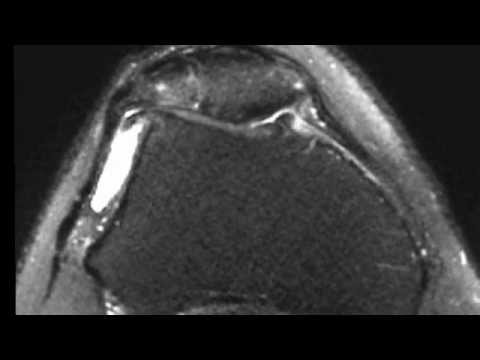

Corps-etrangers et arthrose fémoro-patellaire- genou et IRM :

comment soigner oedeme osseux cheville